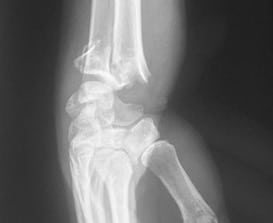

Lésions ligamentaires

Les lésions ligamentaires font suite à une chute sur la main poignet en extension, ou un traumatisme en torsion. Symptômes de poignet douloureux, enflé et perte de force sont révélateurs. Examen clinique, interrogatoire et radiographie, permettent de poser le diagnostic d’une lésion ligamentaire. Le scanner permet de le confirmer et de constater une perforation éventuelle.

Trois ligaments peuvent être atteints :